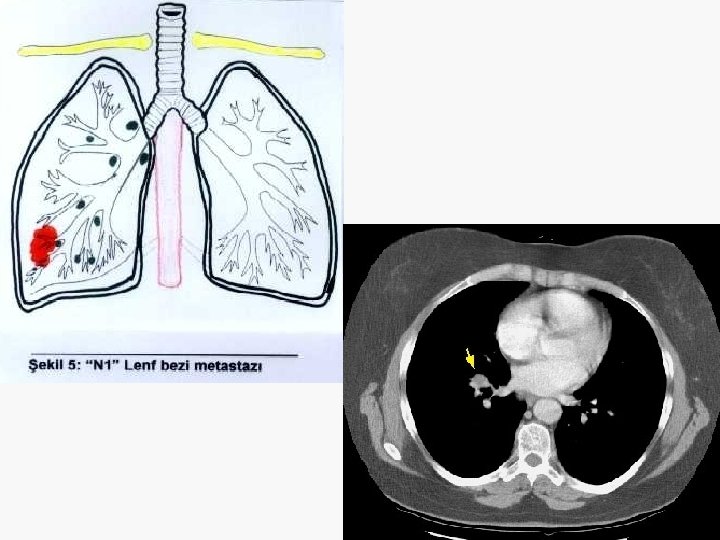

5. 4 cm

Evreleme EVRE 0 : Tis N 0 M 0 EVRE IA : T 1 N 0 M 0 EVRE IB : T 2 N 0 M 0 EVRE IIA : T 1 N 1 M 0 EVRE IIB : T 2 N 1 M 0 T 3 N 0 M 0 EVRE IIIA : T 1 -3 N 2 M 0 T 3 N 1 M 0 EVRE IIIB : T 4 N M 0 T N 3 M 0 EVRE IV : T N M 1